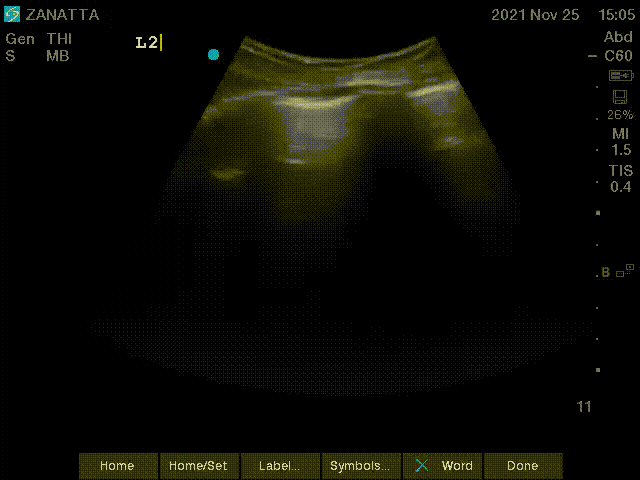

You begin your POCUS assessment with imaging of the left and right lungs.

Left Lung Views